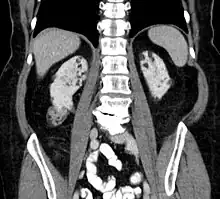

Between 60 and 80% of people with tuberous sclerosis have benign tumors (once thought hamartomatous, but now considered true neoplasms) of the kidneys called angiomyolipomas frequently causing hematuria. These tumors are composed of vascular (angio–), smooth muscle (–myo–), and fat (–lip-) tissue. Although benign, an angiomyolipoma larger than 4 cm is at risk for a potentially catastrophic hemorrhage either spontaneously or with minimal trauma. Angiomyolipomas are found in about one in 300 people without TSC. However, those are usually solitary, whereas in TSC they are commonly multiple and bilateral.

About 20-30% of people with TSC have renal cysts, causing few problems. However, 2% may also have autosomal dominant polycystic kidney disease.

Very rare (< 1%) problems include renal cell carcinoma and oncocytomas (benign adenomatous hamartoma).